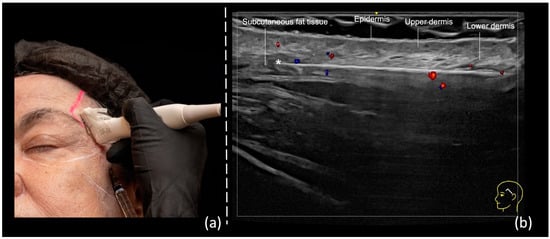

- Scan before injecting: The treatment area is scanned immediately before injection to assess the presence of vessels. The trajectory of the main arteries might be marked on the patient’s skin.

- Scan while injecting: In this case, the cannula is visualized in real time and positioned in the desired anatomical region, avoiding vascular structures.